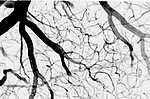

The brain depends on the supply of nutrients by other tissues. Vice versa, it controls all bodily functions. Therefore, a close interaction between the central nervous system and the periphery is required. In addition to classical communication channels provided by afferent and efferent nerve fibers, there is an exchange of messengers and metabolites at the interfaces of brain and periphery. The latter encompass the blood-brain barrier, the blood-CSF barrier and, less known, the tanycytic barrier between circumventricular organs and brain parenchyma. Our group investigates the structure and function of these barriers. Bridging brain barriers could be a key principle in the treatment of brain diseases.